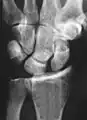

Dynamic instability: Increased scapholunate distance (between yellow lines) upon ulnar deviation of the wrist, but not otherwise.

Dynamic scapholunate instability visible upon clenching the wrist